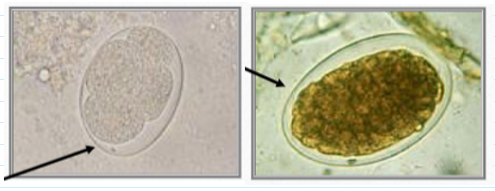

diagnosis of hookworm infection (egg characteristics)

60 x 40 um eggs

Smaller than Trichostrongylus spp

Thin, smooth, transparent, colorless shells

Yolk cells retract leaving clear space

Often difficult to see

trichostrongylus eggs

Must differentiate from hookworm eggs

78-98 x 40-50 um

Larger, elongated compared to hookworm

Slightly pointed